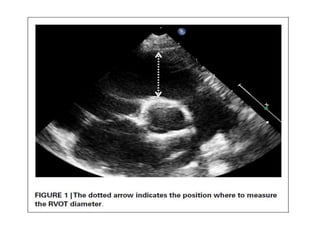

RVOT

• In young patients with good subcostal windows, the RVOT

can be evaluated in the long-axis and short-axis planes and

in the inflow-outflow view.

• Parasternal long-axis and short-axis views facilitates

assessment of the infundibulum and any associated

aneurysm, residual PV tissue, and main and branch PAs.

• The RVOT dimension at the site of the former PV is

important when transcatheter valve implantation is being

considered.